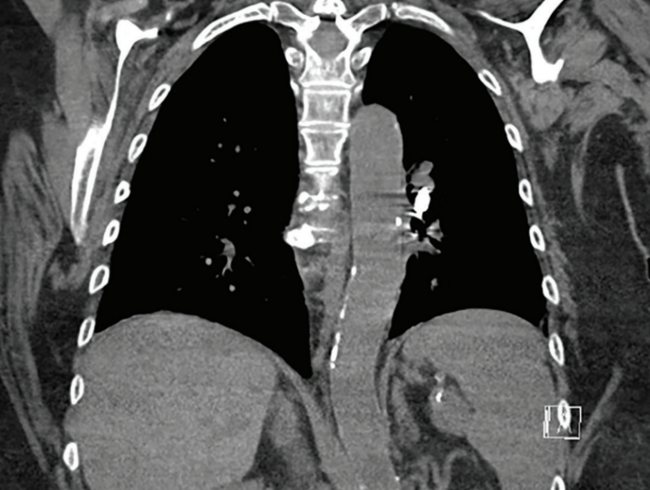

A computed tomography (CT) angiogram of the chest was then performed (Figure 1), which detailed that the device had embolized to a posterior segmental branch of the left lower lobe of the PA.

Additional imaging can also be useful for specifically localizing where the device has migrated within the pulmonary arterial system as well as device orientation, as the docking end is preferable for snaring. The CT scan in this case proved helpful in preprocedural planning.